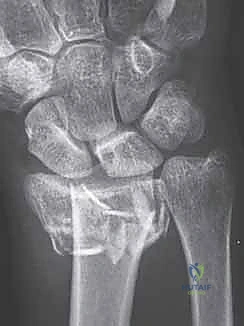

3. رد الكسر (Fracture Reduction)

هذه هي المرحلة الأكثر حساسية. يقوم الدكتور بإعادة القطع العظمية المتفتتة إلى مكانها التشريحي الأصلي بدقة متناهية. يتم استخدام جهاز الأشعة اللحظي للتأكد من أن سطح المفصل أصبح أملساً ومستوياً تماماً. في بعض الحالات التي يوجد فيها نقص عظمي نتيجة التفتت، قد يستخدم الدكتور هطيف طعوماً عظمية (Bone Grafts) لملء الفراغات.